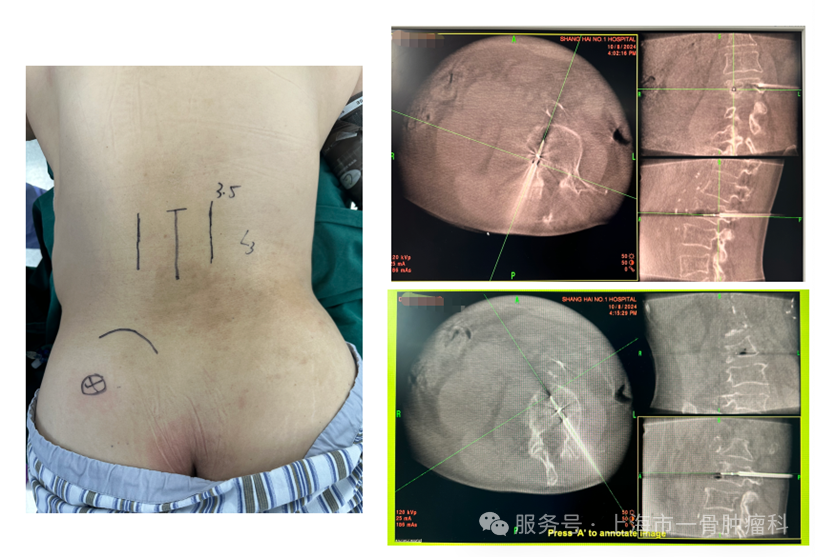

图2:术前腰椎CT:L3椎体混合型骨质破坏伴椎旁受累

图4: L3椎体双侧OC射频消融+骨水泥成型

图5: L3椎体微创消融术后